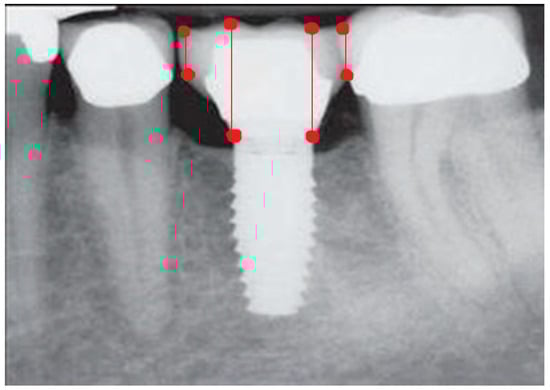

- Measurement of mesial and distal bone loss: Clinically, an increase in the probing depth of the peri-implant pockets, both mesial and distal, was recorded using a calibrated probe with a force of 0.25 N. Radiographically, mesial and distal peri-implant bone height loss was measured using properly performed radiological projections. In fewer than five patients, statistically significant findings in cases of bone loss were difficult to achieve.

- Measurement of the mesial and distal cantilever: The mesial cantilever was significantly greater for the bilateral bone loss group (1833.5 ± 1531.4 µm) compared to the group without MBL (1029.5 ± 968.6 µm) (F = 2.77; p < 0.05). Concerning the effect of the mesial versus distal cantilever, although the mesial cantilever appears to be more favorable, the only article found in the literature regarding this finding is a study by Romeo et al. (2003), which showed that this effect is not always consistent, although the difference is minimal [31].